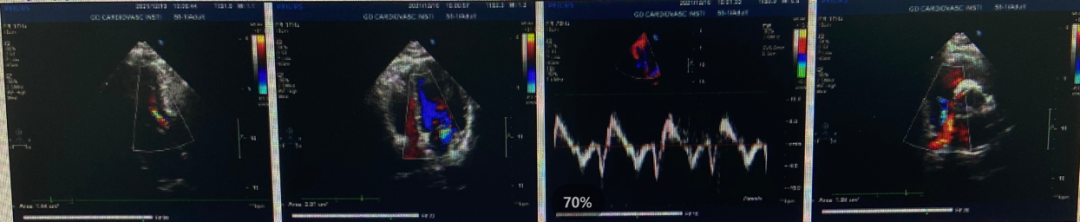

心脏彩超左房轻度扩大,室间隔轻度增厚,升主动脉轻度增宽并主动脉瓣轻度反流。

心电图正常,心彩超提示轻度二尖瓣返流,轻度主动脉瓣返流,轻度三尖瓣返流。

手术影像

LAD、LCX双支 CTO ,LAD 近端50%狭窄

RCA粗大,支架代偿良好。远端60%狭窄,PDA开口80%狭窄